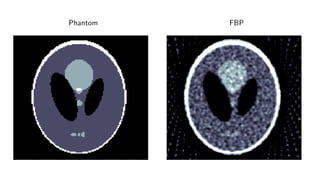

Results

ellipses

Results for ray transform inversion in 2D.

Inverse problem:

g = P(f ) + δg

Geometry: Parallel beam, sparse view (30 angles)

Noise: 5% additive Gaussian

Data: 128 × 128 pixel ellipses

Compare to:

FBP

Total Variation

Post-processing deep learning by U-Net

Phantom Training Phantom

Phantom FBP

Quantitative

Method PSNR (dB) SSIM Runtime (ms) Parameters

FBP 19.75 0.597 4 1

TV 28.06 0.928 5 166 1

Learned U-Net 29.20 0.943 9 107

Learned Primal-Dual 38.28 0.988 49 2.4 · 105

Comments

Very large quantitative improvement =⇒ PSNR not good metric

Noticable visual improvement

Speedup enables clinical implementation

We are remarkably close to the theoretical optimum